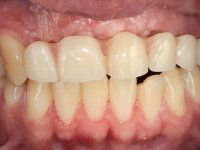

Paciente do sexo masculino, com 22 anos de idade e não fumador. Apresentou-se na consulta 6 meses após um acidente de viação em que perdeu os dentes 21, 22, 23 e 24. Os dentes 12 e 11 apresentavam mobilidade grau 3 apresentando-se também com extracção indicada. A arquitectura gengival da zona desdentada apresentava-se retraída e planificada.

O paciente foi observado conjuntamente e a dúvida que surgiu de imediato foi se seria possível com a regeneração óssea a efectuar poder ser reabilitada naturalmente a zona das papilas interdentárias. Nesse sentido foi feito um enceramento de diagnóstico que contemplaria as duas hipóteses, utilizando ou não a cerâmica gengival. A confecção desse enceramento foi fundamental para expor ao paciente a dificuldade da reabilitação. O wax-up deu origem a um mock-up que foi aprovado pelo paciente e que simultaneamente serviu de guia imagiológica. O caso foi planificado cirurgicamente e realizada uma guia cirúrgica com que foram colocados os implantes. Após 10 semanas foi feita a 1ª impressão para confecção da ponte provisória. Foram criados os primeiros perfis de emergência na gengiva artificial e foi digitalizado o modelo. Por processo de CAD-CAM foi confeccionada uma ponte provisória aparafusada baseada no enceramento de diagnóstico. A ponte trabalhou durante 8 semanas os tecidos moles que foram fielmente copiados numa impressão com técnica de moldeira aberta. Os transferes foram individualizados com resina composta para copiarem fielmente os perfis de emergência criados pela ponte provisória. Confeccionado o modelo de trabalho definitivo, foi realizada uma infra-estrutura em zircónio seguindo a orientação do enceramento de diagnóstico. O assentamento da infra-estrutura foi testado em boca e simultaneamente foi novamente impressionados os tecidos moles com um silicone fluido. Nessa consulta foi feito o levantamento da cor. Os dentes 13 e 23 apresentavam uma saturação anormalmente forte que resolvemos não valorizar, optando por privilegiar a relação com o sector antero-inferior. Foi realizada uma nova gengiva artificial com a impressão que acompanhou a impressão de arrasto com a infra-estrutura. Após a colocação da cerâmica na infra-estrutura foram coladas as meso-estruturas. O trabalho final foi aparafusado lentamente permitindo a adaptação dos tecidos moles.